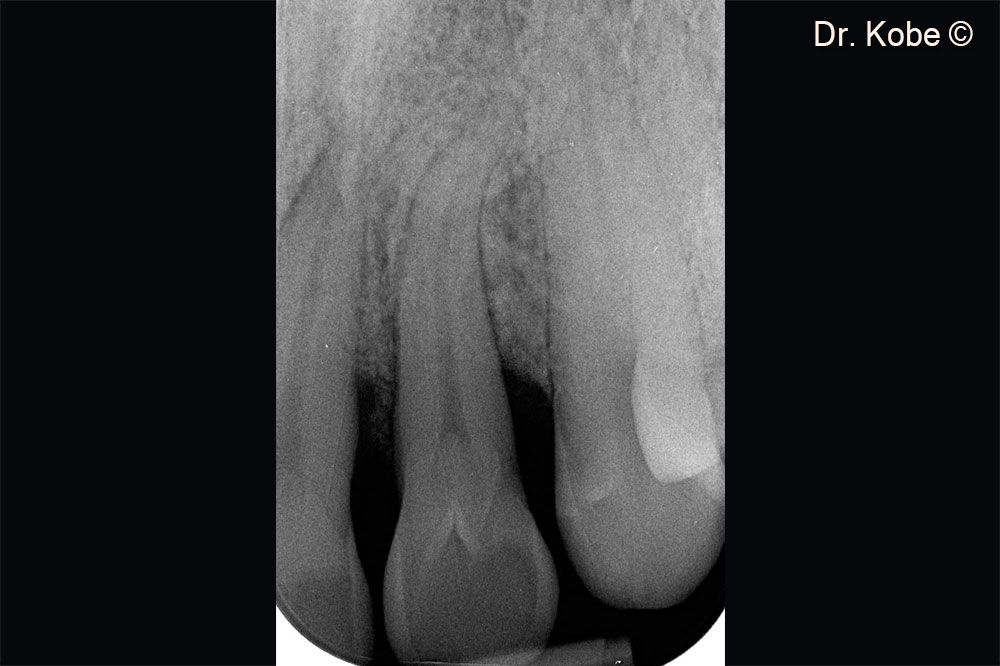

Hình ảnh X-Quang sau một năm điều trị